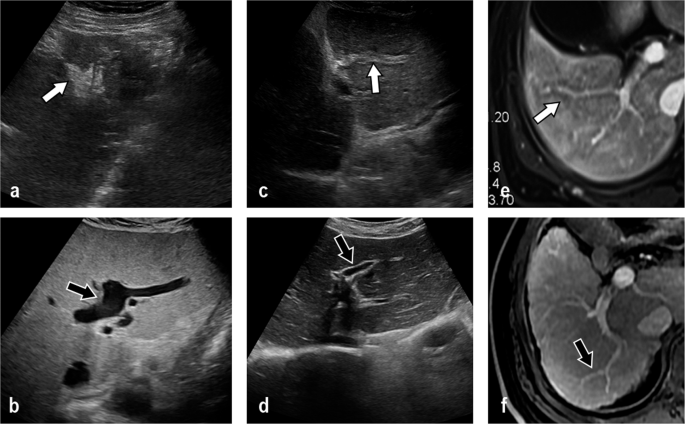

What is a liver flowSPECT. Because of the high target-to-background contrast obtained with single photon emission computed tomography SPECT normal intrahepatic vessels approximately 2 cm in diameter may appear as distinct focal defects in tomographic sections throughout the liver even though normal vessels rarely cause such defects on planar images. I DO HAVE THE ANSWER CHOICES BUT I FELT LIKE IF I POSTED THEM ALONG WITH QUESTIONS IT WOULD OF THREW.